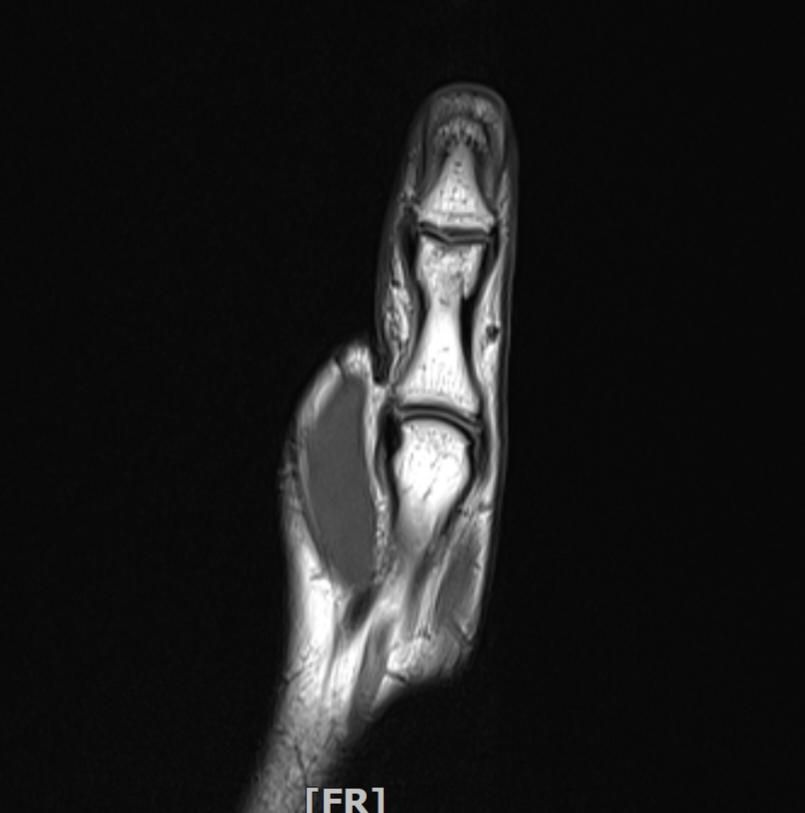

mri 엄지손가락 미세골절 여부확인

공구에 왼손이 말려서 엄지를 다쳤습니다 응급실에서 부목고정 조치후 이틀후 mri촬영 하였습니다.

엄지손가락 뼈가 자주 욱씬거리는데 미세골절 여부 확인 부탁드립니다.

• 3번 째 사진

Mri는 연부조직 확인에 강하지만 미세 골절은 일반적으로 엑스레이나 CT에서 더 잘보입니다. 다만 골수 부종이 보인다면 골절 가능성을 시사할 수 있습니다 mri판독 결과에서 골절선이나 골수 부종 유무를 확인해야 정확한 판단이 가능합니다. 정확한 진단은 반드시 영상의학과 전문의의 판독을 통해 받아야 합니다!

우선 현재로썬 MRI 사진으론 정확한 판단을 하긴 어렵지만 주변 연부조직의 손상이 보여집니다.

다만 미세골절 같은 경우는 여러 방면의 판독이 필요하므로 정확한 판독은 병원에 내원하셔서 MRI 촬영을 한 병원에 판독지를 받으시고 전문의에 판독을 받으시길 적극 추천드립니다.